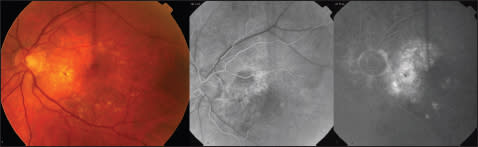

In December 2004, the left eye was found to have occult subfoveal CNV on fluorescein angiography (Figure 1), which was observed as the patient maintained a stable visual acuity of 20/25. However, in September 2005, the patient presented due to a decrease in VA of the left eye to 20/200 and was found to have progression of the occult neovascularization with fluid under the retina on optical coherence tomography (Figure 2).

Figure 1. Fundus photos and FA of left eye in 2005, showing RPE changes, drusen and an occult CNV. FA shows early mottled hyperfluorescence centrally, followed by a late, stippled hyperfluorescence consistent with an occult CNV.